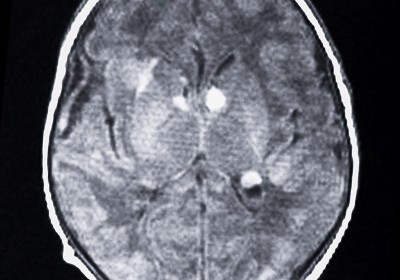

- Tuberes corticales (tumores pequeños en cerebro), hasta en el 95-100% de los pacientes, de estos hasta el 90% en lóbulo frontal y 95% de los casos son múltiples. En la mayoría de los casos son los causantes de las crisis convulsivas en los pacientes con esclerosis tuberosa (estas se presentan hasta en el 90% de los pacientes). Se detectan con estudio de resonancia magnética cerebral.

- Nódulos subependimarios (tumores hamartomatosos benignos en cerebro), hasta en el 90-100% de los pacientes con esclerosis tuberosa, la mayoría de las veces se encuentran calcificados y en la región del agujero de Monro. Se detectan con tomografía cerebral.

- Astrocitoma de células gigantes (tumor en cerebro), se reporta en el 1 al 26% de los pacientes con esclerosis tuberosa, suelen ser benignos y la localización es en el agujero de Monro, la edad de presentación más frecuente es entre 8 y 18 años, son mas grandes comparados con los nódulos subependimarios (>1cm) ya que la localización suele ser la misma.